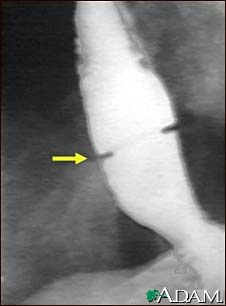

Schatzki ring - X-ray

A solution containing a dye (barium), which is visible on X-rays, has been swallowed (upper GI series) and X-rays have been taken of the esophagus. There is a narrowing near the stomach (indicated by the arrow). This non-cancerous ring of tissue (Shatzki's ring) may cause swallowing problems (dysphagia) and can be treated with dilation of the stricture.